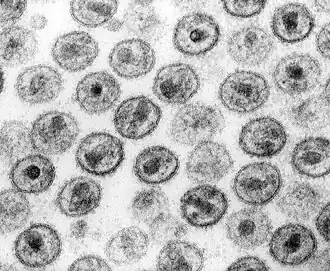

HI-Viren im TEM | ||||||||||||||||||||||

HIV-1, das insgesamt häufiger ist, und HIV-2 ähneln sich prinzipiell hinsichtlich des klinischen Infektionsverlaufs und der krankmachenden (pathogenen) Eigenschaften, auch wenn die Infektion mit HIV-2 wohl insgesamt langsamer verläuft. Die beiden Stämme sehen unter dem Elektronenmikroskop gleich aus, unterscheiden sich jedoch in der molaren Masse der Proteine und in der Anordnung und Nukleotidsequenz der Gene. HIV-1 und HIV-2 entstanden aus unterschiedlichen Typen der bei bestimmten Affenarten vorkommenden SI-Viren. HIV-2 wurde überwiegend in Westafrika nachgewiesen.[48]